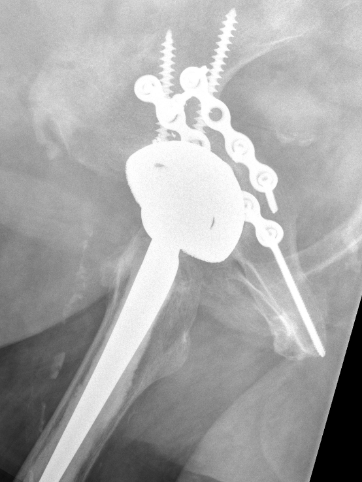

Intra-operative acetabular fracture

Postoperative acetabular fracture treated with double posterior plating

- plate posterior column if fractured

- screw fixation anterior column

- additional screws in cup +/- cage

- touch weight bear for period